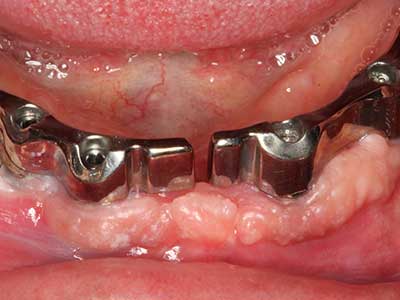

Aplicación: Partición ósea / Cortical Split

El tejido óseo no solo tiene un contenido puramente mineral, sino que también presenta una importante proporción de fibras de colágeno. Esto no solo garantiza una buena resistencia a la presión, sino también una cierta flexibilidad, que puede aprovecharse para la realización de aumentos. En la plastia de expansión clásica a efectos de una partición ósea, la cresta maxilar atrofiada se divide en su eje longitudinal y, tras alcanzar una profundidad de osteotomía suficiente, se extiende con cuidado (fig. 13-16), en un caso ideal sin desperiostizar de forma visible el maxilar (Brugnami, Caiazzo et al. 2014, Stricker, Fleiner et al. 2014). Los sistemas de tornillos y placas con distancia de expansión creciente han demostrado su eficacia para distanciar entre sí las dos tablas óseas por debajo del umbral de rotura. Por regla general, se requieren anchuras de hueso residual de al menos 3 a 4 mm (Chiapasco, Zaniboni et al. 2006) para garantizar una flexibilidad y una cobertura ósea suficientes de los implantes que van a incorporarse. En caso necesario, una osteotomía de descarga vertical unilateral o bilateral puede mejorar la flexibilidad. Como alternativa a la técnica clásica se ha descrito una combinación con otras técnicas de aumento, sobre todo en la parte bucal.

Con el uso de sierras piezoeléctricas la división se efectúa de forma especialmente cuidadosa y sin pérdidas importantes de las dimensiones, por lo que no se han encontrado diferencias significativas entre los implantes realizados en el maxilar dividido y en la cresta alveolar no deficitaria (Chiapasco, Zaniboni et al. 2006, Danza, Guidi et al. 2009). No obstante, precisamente en la partición profunda y limitada de forma local, es preciso asegurarse de que exista una adecuada irrigación por agua para evitar que se produzcan sobrecargas térmicas en las áreas de osteotomía apical.